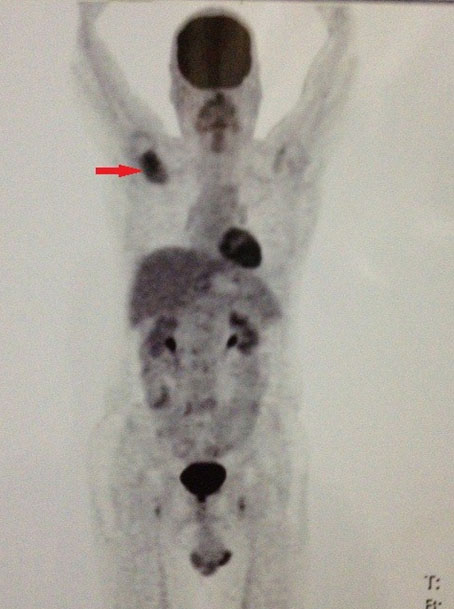

A 62-year-old man presented with pain and gradually increasing swelling of the right scapular region for four months. On examination, there was a bony hard swelling on the scapula with no restriction of movement. Magnetic resonance imaging (MRI) showed a destructive lesion in the spine of the scapula (Figure 1). Whole body 18-Fluoro-deoxy-glucose positron emission tomography (FDG-PET) showed a non-FDG avid lesion in the spine of the scapula, with no other metabolically active lesion identified elsewhere (Figure 2). The spine of the scapula was surgically resected with adequate margins. Histopathology revealed a neuroendocrine tumor (NET). Lesional cells showed diffused string immunopositivity for pan cytokeratin (pan CK) an epithelial cell marker and markers of neuroendocrine differentiation, chromogranin and synaptophysin (Figure 3). Upper and lower endoscopies were negative for a primary gastrointestinal NET. Postoperatively, the patient did not receive any adjuvant therapy. The patient was followed up over four years and has remained disease free, clinically and radiologically.

Figure 2: Whole body PET-CT scan showing a non-FDG avid localized lesion in the spine of the scapula with no other metabolically active lesion identified elsewhere.